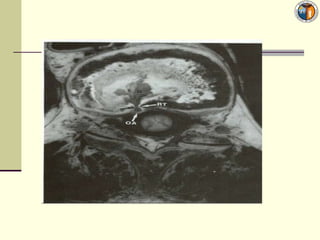

Cauda Equina syndrome

Lumbociatica bilateral o sindromeCauda equina  Descartar compromiso masivo o cauda equina que tiene compromiso esfinteriano vesical y pérdida sensibilidad en silla de montar. Es de mal pronóstico, es urgencia, muchos quedan secuelados. Su fc es de 0,04% de los casos  Saber que en general se dividen en HNP (95%) y no HNP; (tumores oseos, tumores sns, congenitas, espondilositesis, estenorraquis,etc)  SI UN PACIENTE NO PUEDE CAMINAR Y NO CONTROLA ESFINTER HOSPITALIZAR POR SER EMERGENCIA NEUROQX